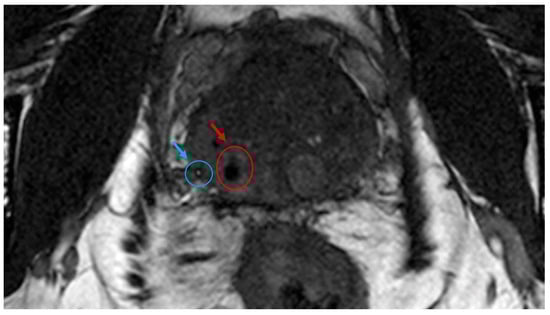

3.4. Visibility of NOVA Markers in a Clinical Case